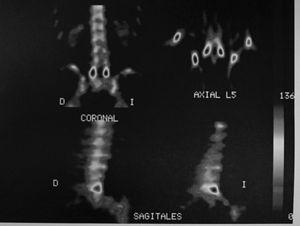

Als 15 dies el pacient es presenta amb simptomatologia atenuada. La GOP/SPECT (figs. 3 i 4) demostra fenòmens de remodelació òssia al nivell d'ambdues pars d'L5. Per tant, es conclou el diagnòstic d'espondilòlisi activa L5 dreta i espondilòlisi esquerra en formació. Es continua el mateix tractament i s'hi afegeix una pauta específica d'exercicis deslordosants i ortesis plantars de correcció.

Figura 3

Figura 4